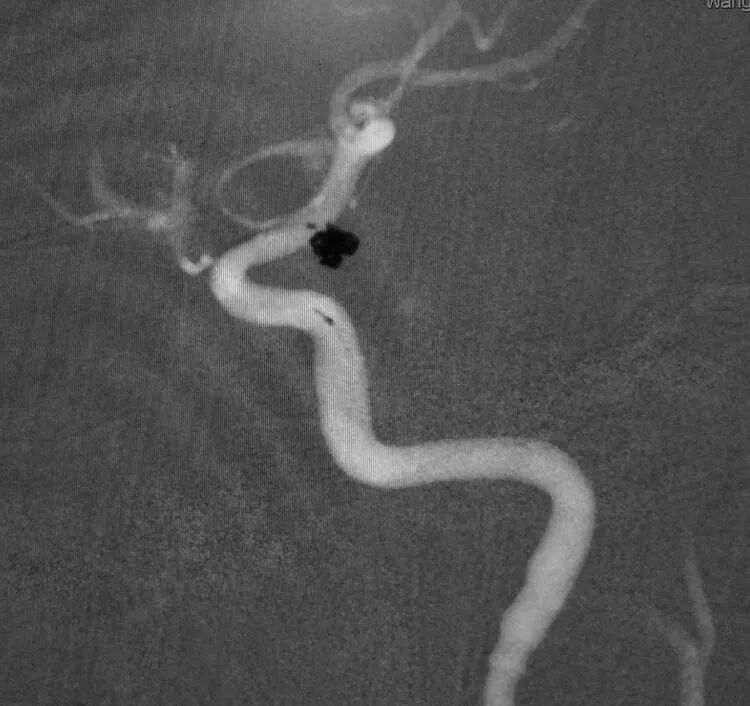

扁平状的前交通动脉瘤

仍然用双微管技术栓塞,一根直头微导管进入瘤体上部,另一根微导管头端塑成C形进入瘤体下部,分区栓塞该瘤